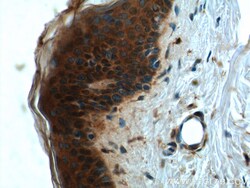

- Submitted by

- Main image

- Experimental details

- Immunohistochemistry of paraffin-embedded human skin tissue slide using 21869-1-AP (CCHCR1 Antibody) at dilution of 1:50 (under 40x lens).